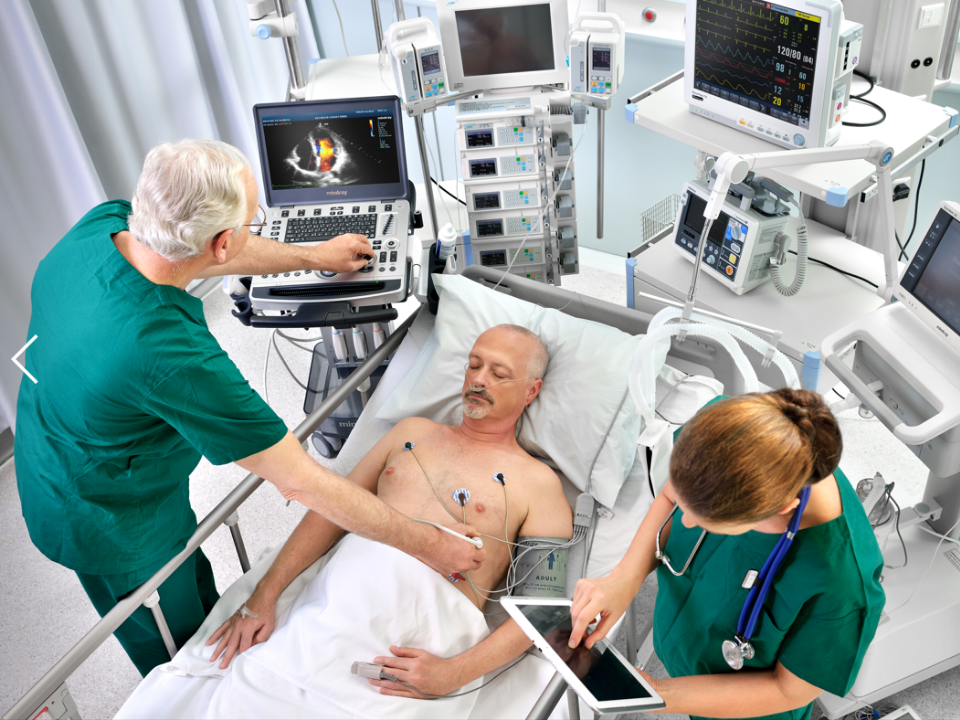

Mehr Mobilit?t muss nicht zu Lasten der Leistung gehen. Der M9 z?hlt mit seinen hoch?entwickelten Funktionen, die ĂŒblicherweise nur in schweren Standger?ten zu finden sind, zu den fortschrittlichsten Premium-Sonographiesystemen im Laptop-Format. Dank der Ultraschallplattform mQuadro hebt das M9 den Branchenstandard auf ein Topniveau.

- Kompakt und effizient

- Vielseitig